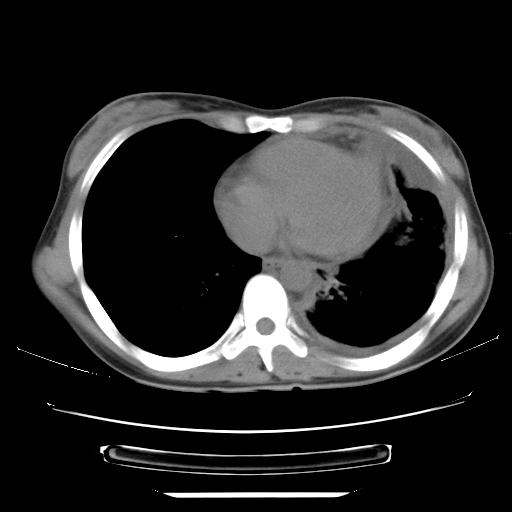

女,29岁,胸部不适,在外院胸片提示胸腔积液,到我院ct检查。

纵膈窗

左肺上叶不张,左侧胸水,叶间裂积液,纵隔淋巴结,脾脏钙化,考虑左肺上叶支气管内膜结核,结核性胸膜炎,脾结核

支持两肺继发性肺结核,左侧胸膜腔包裹性积液、胸膜肥厚,脾内多发钙化(结核钙化)。

支持 两肺继发性肺结核,左侧胸膜腔包裹性积液、胸膜肥厚;脾内多发钙化(结核钙化)。

两肺继发性肺结核,左侧胸膜腔包裹性积液、胸膜肥厚;脾内多发钙化(结核钙化)。支持!